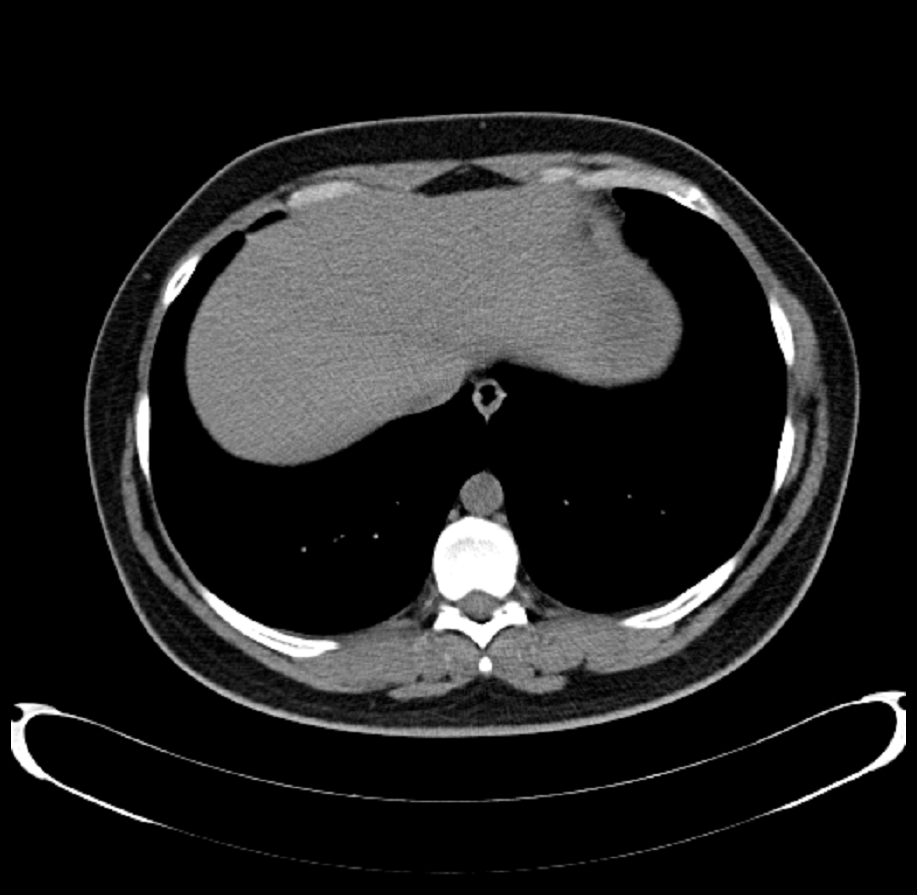

Standard adult abdominal phantom with liver, kidneys, spleen, and bowel